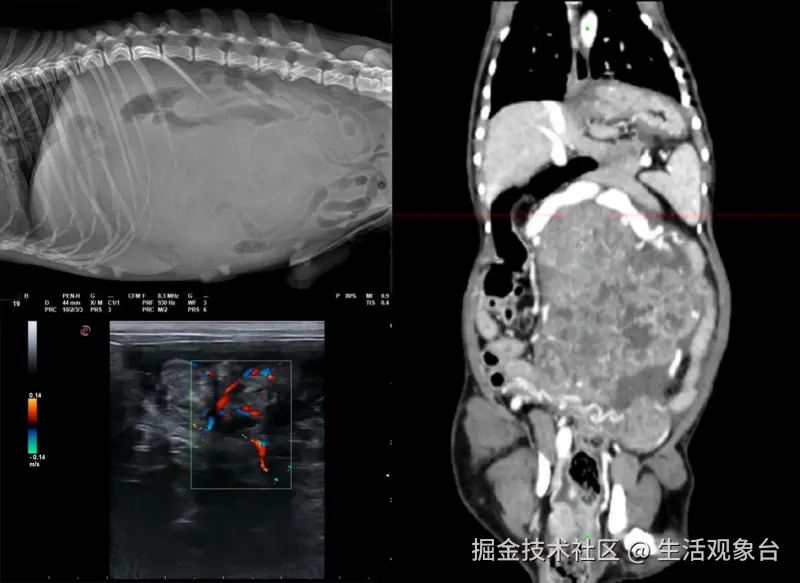

张晓远老师曾接诊一例14岁公犬“鹏鹏”,该犬就诊前近一月出现情绪暴躁、腹围增大并伴随腹部疼痛的情况。凭借敏锐的临床洞察力,张老师迅速将诊断重点指向影像学评估。

在体格检查发现中腹部团块、且左侧阴囊睾丸缺失的基础上,张医生系统部署了X线、超声及增强CT三重影像检查。影像结果显示:中腹部团块边界清晰,增强CT进一步揭示其内部强化不均匀,周围伴有明显血管灌流——这一系列典型的影像学特征,高度提示腹腔内隐睾及相关肿瘤性病变的可能。基于影像判读,给予临床倾向诊断,术前评估为ASA 3级。张晓远老师在完善术前管理后,为患犬施行手术切除患处,术后病理证实为弥漫性支持细胞瘤,与其前期根据影像学判断完全吻合。

该病例的难点在于通过多模态影像的综合分析,在不开腹的情况下精准判断肿物性质、位置及其血供特点,为高风险高龄犬只制定安全手术方案。张晓远老师在此过程中,展现出深厚的影像解读能力、跨模态影像整合分析水平,以及将影像发现转化为手术决策的临床执行力。

鹏鹏术后恢复良好,病痛显著缓解。本案例也充分体现了精准的影像学评估不仅是诊断腹部复杂肿物的关键,更是高龄动物成功接受外科治疗的重要保障。